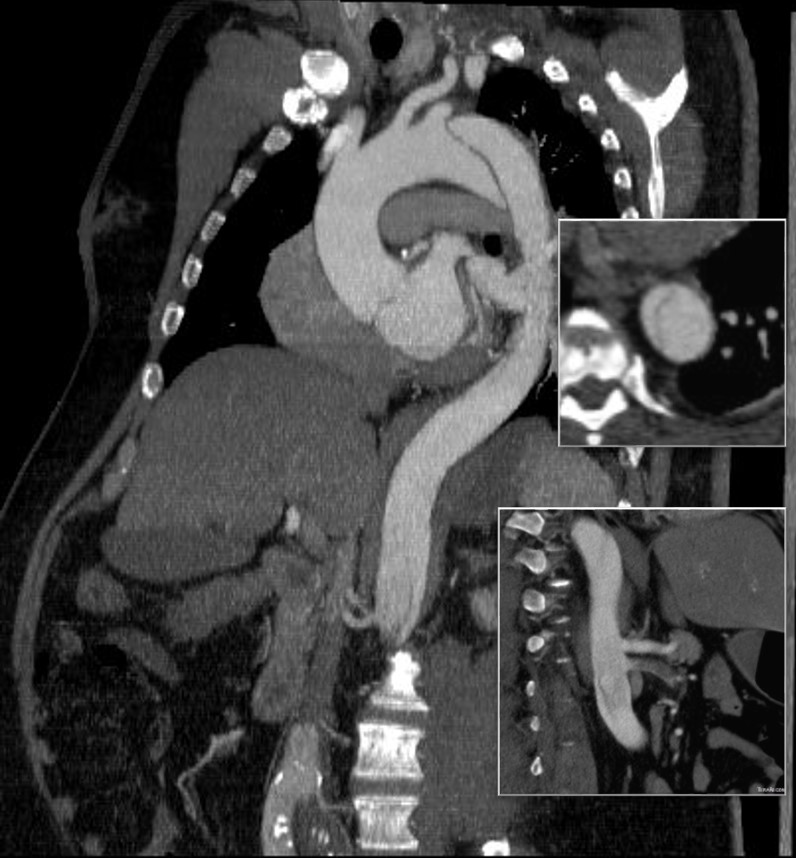

The patient had a 8cm sphere shaped aneurysm arising in the transdiagphragmatic aorta, leaking into the right pleural cavity.

The patient was otherwise a healthy middle aged man with risk factors of smoking and hypertension. The centerline reconstructions showed the thoracic aorta above the aneurysm to be around 20mm in diameter and same below, with the celiac axis and superior mesenteric artery in the potential seal zone of a stent graft. The only plaque seen was around the level of the renal arteries and was focal and calcified. Looking at the list I had made as a comment to the Linked-In post, I realized that I really only had one viable option.

Open repair, usually the most expeditious option, was made challenging by the right hemothorax, making a left thoracotomy hazardous if the lung had to be deflated. Cardiopulmonary bypass would have to be arranged for, and that adds a metabolic hit that greatly raises the stakes. Of the endovascular solutions, the only viable option was TEVAR to exclude the rupture and debranching of the celiac axis and superior mesenteric artery. To those who would advocate for parallel grafts, there was no room in the normal 20mm diameter aorta. And branch systems for rupture are some time in the future. Also, the patient was becoming hypotensive. So the planned operation was first TEVAR to stop the bleeding, and then open surgical debranching. A hybrid repair.

The smallest stent graft we have is a 21mm graft, but it would not be suitable for this aorta. In practice, the normal aorta is quite elastic and will dilate much more than what is captured on a CTA. The next size we have is 28mm graft and I chose this to exclude the rupture, which was done percutaneously.

As seen below, the graft excluded the celiac and SMA. Late in the phase of the final aortogram (second panel) there was an endoleak that persisteed despite multiple ballooning. The timing suggested the intercostals and phrenic vessels contributed to a type II endoleak, but it was concerning.